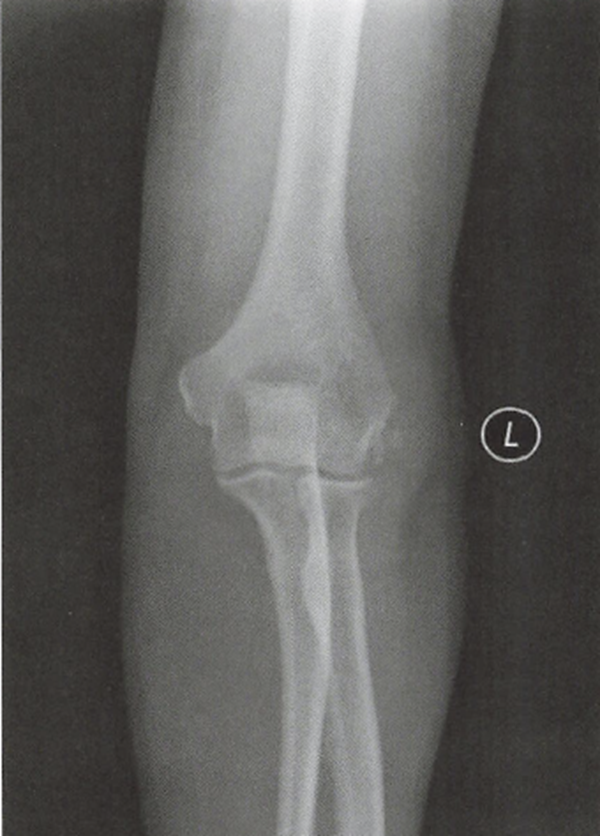

(1)X线平片

常规正、侧、轴位X线平片少有异常发现,但可以排除肘关节的合并疾病,如骨关节炎时关节后外侧旋转不稳定等。偶尔会发现钙化性腱鞘炎。